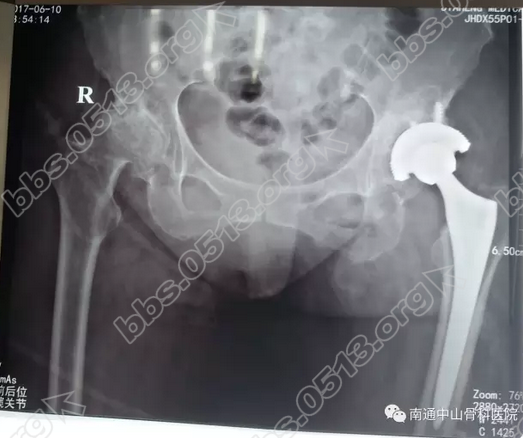

6月8日,王女士进入手术室接受“左侧人工髋关节置换术”。手术由我院胡玉华院长主刀、丁荣清医师等协助配合,由于手术区域解剖极其复杂,手术难度较大,胡院长十分谨慎有序的将手术层次做到步步分明,熟练精准。2个小时后,手术顺利完成。. b% c0 \1 v; Z6 j8 L. g9 {( w& g0 [1 ?

2.png

4 G7 g+ Z' s9 Z" n8 L: T  术后,王女士严格按照我院医师的医嘱进行疗养。治疗至今,疗效显着。王女士的疼痛已经明显减轻,再过段时间,她的腿可以下地站立了。